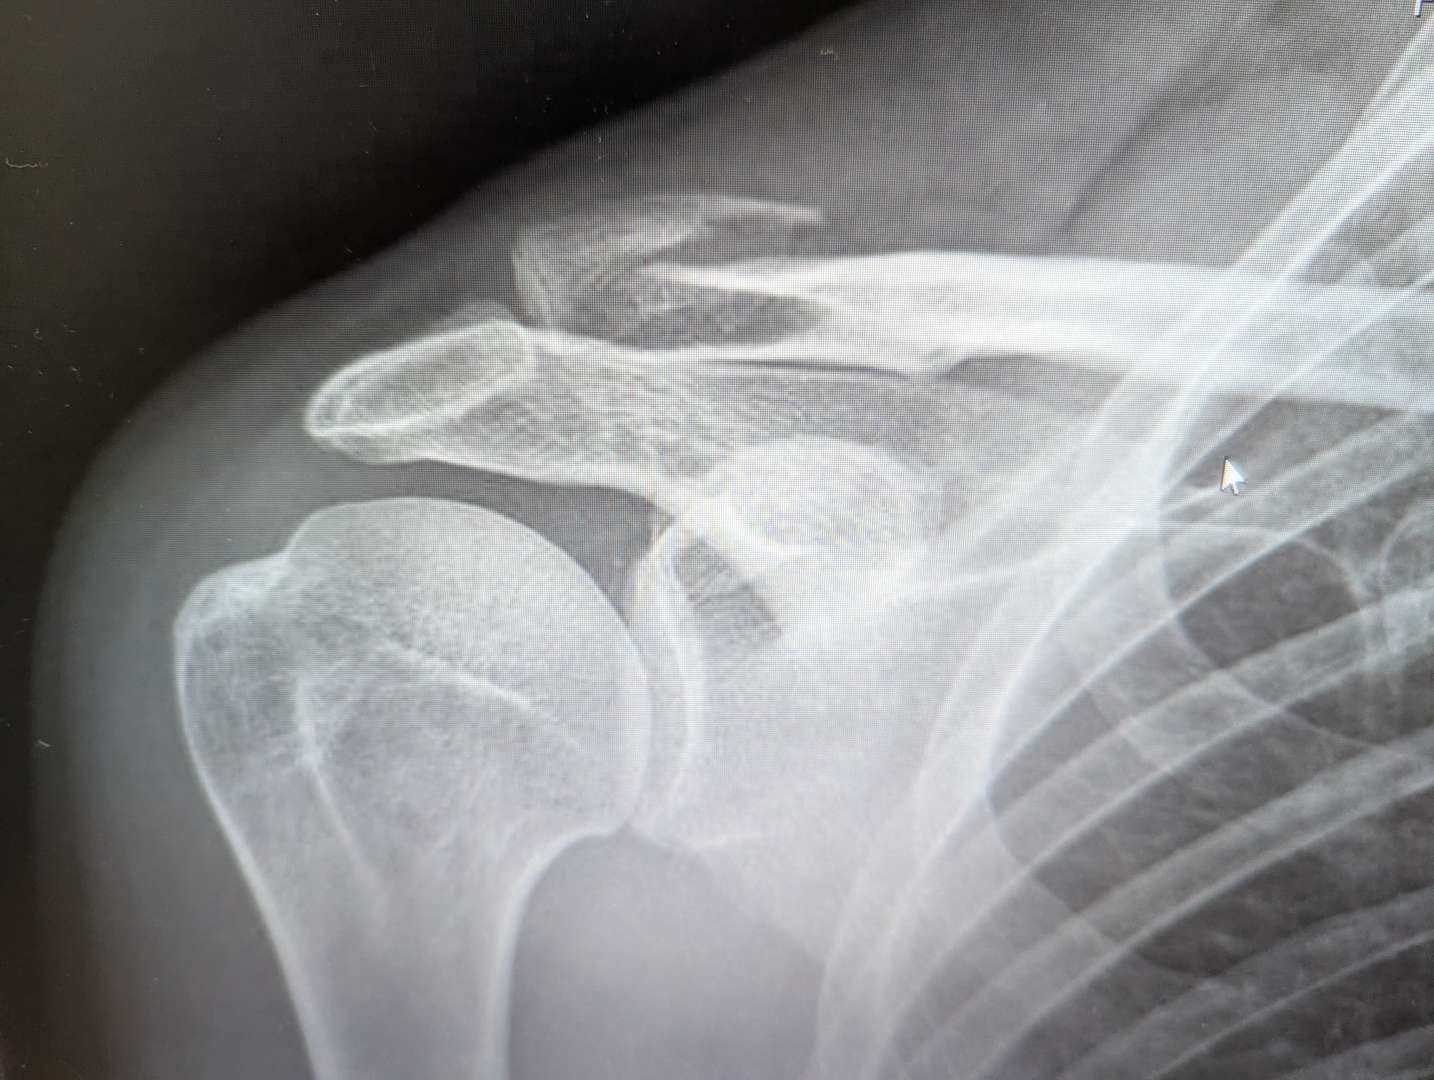

So I went to fracture clinic. Consultant and another doc. Absolutely zero interest in plating it as bone not pushing through skin. View was it would rejoin - I look at that xray and think "Really?". Anyway back in three weeks, if it's not healing they'll plate it.

Part of me thinks this is good- give it the chance to heal and if not have the op anyway. Part of me thinks that's 4 weeks in a sling followed by another 2 weeks post op and I'd defo then miss out on a trip to Ainsa early October. I'm going to sleep (well stay awake mostly) on it but think a 30 minute private consultation with a doc I've been recommended would at least give me some verification o or otherwise of what I've been told.